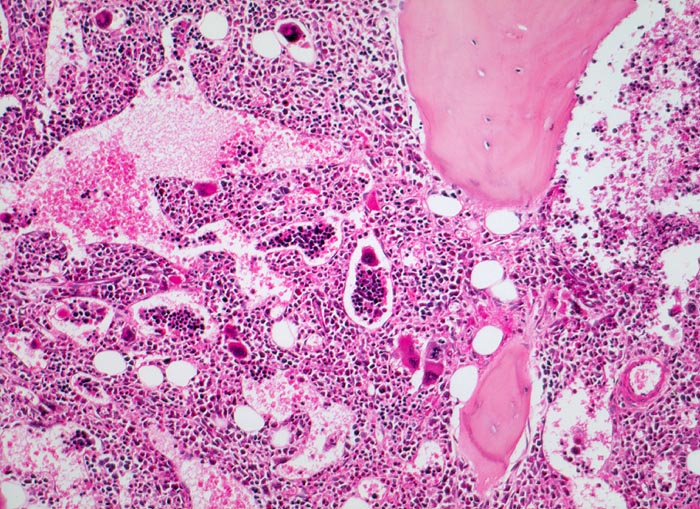

Die Erkrankung ist charakterisiert durch Knochenmarkfibrose, Hepato-Splenomegalie und extramedulläre Blutbildung. Diese findet sich am häufigsten in Leber und Milz, seltener in Lymphknoten, Nieren, Nebennieren, Dura mater, Gastrointestinaltrakt, Lunge, Mamma oder Haut. Blut und Knochenmark sind immer involviert. Die Krankheit entwickelt sich über ein initiales präfibrotisches Stadium mit hyperzellulärem Knochenmark zum fibrotischem Stadium (vorliegendes Präparat). Das fibrotische Stadium ist gekennzeichnet durch eine Vermehrung von Reticulin- und/oder Kollagenfasern und oft einer Knochenneubildung (=Osteomyelosklerose). Die Zellularität des Knochenmarks ist dann vermindert und dilatierte Marksinus enthalten intraluminale Blutbildungsherde. Es besteht eine auffallende Proliferation von Gruppen bildenden atypischen Megakaryozyten.

• Osteosklerose: verplumpte und breite Knochenbälkchen.

• Kollagenfibrose.

• Dilatierte Sinusoide mit intrasinusoidaler Blutbildung.

• Vermehrung von atypischen, in Gruppen liegenden Megakaryozyten mit abnorm lobulierten Kernen.